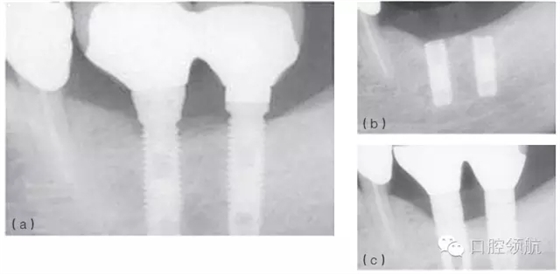

例如,在發(fā)生率低的種植體折斷病例中,感染和創(chuàng)傷經(jīng)常同時存在,或相繼發(fā)生。感染引起的種植體周骨喪失(種植體周圍炎)也可能導(dǎo)致種植體折斷。過載或創(chuàng)傷則是種植體折斷的第二個因素,種植體折斷的高度常常與骨-種植體的接觸水平相一致(圖6.4a~c)。也可相反,種植體周感染繼發(fā)于咬合創(chuàng)傷,導(dǎo)致種植體不能形成骨結(jié)合而失敗。(圖6.5a~c)

圖6.4 (a)18號、19號位點種植體出現(xiàn)邊緣骨吸收。(b)2年后出現(xiàn)折斷。(c)拔除了舊的種植體,新的種植體植入并進(jìn)行修復(fù)。